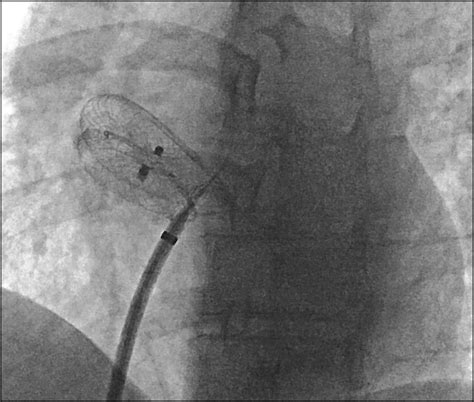

640×640

researchgate.net

Fluoroscopic view (LAO 30/2 degrees) showing Amplatz P…